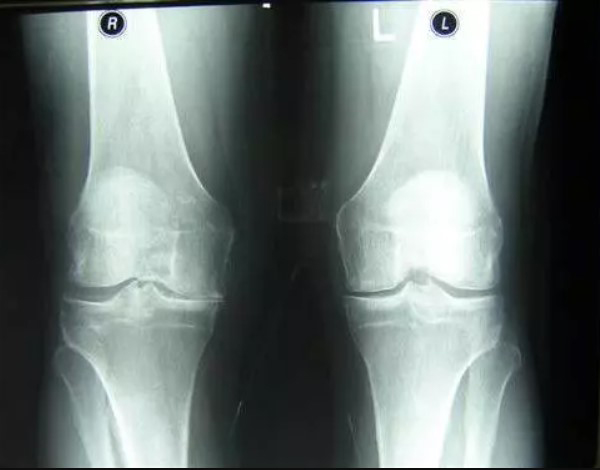

Cuando vi las estadísticas sobre enfermedades articulares en colombia, me asusté. ¿Sabe cuál es la causa más común de discapacidad en colombia? No es el cáncer, el SIDA ni la diabetes — ¡es la artrosis! La artrosis más común, que en Japón puede resolverse en 2 o 3 semanas con una fórmula relativamente barata y accesible, lleva a la discapacidad en colombia.

Las enfermedades articulares que en colombia se intentan diagnosticar por separado, hace tiempo que en Japón se unificaron bajo una sola condición: "Depósito de sales en las articulaciones". Esta condición incluye:

- Gota

- Artritis

- Artrosis

- Osteocondrosis

- Reumatismo

- Osteoporosis

- Bursitis

- Sinovitis

- Quiste sinovial

Esta es una lista muy resumida, pero las demás enfermedades son simplemente subtipos de estas nueve patologías principales. Por ejemplo, la coxartrosis es un subtipo de artrosis, y así sucesivamente.